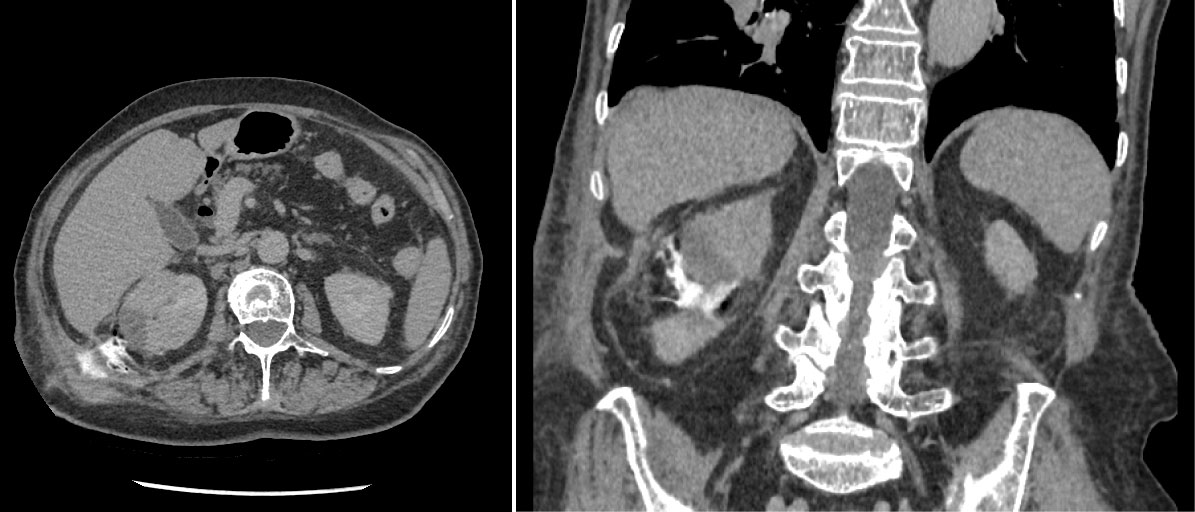

75-years-old woman presented with right kidney tumor using ultrasound. Two tumors were detected on CT (Figure 1). The conclusion of a CT scan: In the right kidney mid/lower pole 16 mm in diameter hypervascular tumor, more endophytic, about 7 mm till the collecting system of the kidney (Nephrometry scale 5a). The second tumor in the right kidney is approximately 37 × 28 × 44 in size, located in the upper/mid thirds of the kidney, more laterally, polycyclic, nonhomogeneous with necrosis, unevenly accumulates contrast agent, more endophytic, in contact with collecting system of the kidney. A biopsy was performed. Moderately-differentiated (G2) papillary adenocarcinoma, I type was found. Under intravenous anesthesia, percutaneous ultrasound-guided microwave thermal ablation was carried out. Under ultrasound guidance two short tip needles were inserted into the tumors and microwave thermal ablation was performed for 15 minutes using 35 W. The tumors changed in visually as were seen on ultrasound. The needles were removed after procedure. No perioperative or post-operative complications were observed. After 2 weeks a large amount of urine began to leak through the puncture site on the right flank. Approximately 1.5 l of urine on a daily basis. CT was performed: Fistula from the mid calyx was found (Figure 2). Collection of fluid around the fistula, by the abdominal wall. It was decided to put a stent in the right ureter. Nephrostomy was technically impossible due to the absence of hydronephrosis. Because of ureteral stenosis, ureteroscopy was unsuccessful. Right ureteral stenting was performed under the X-ray control. Position of the stent was appropriate. The patient was released home. There was no urine coming through the fistula, but after two weeks, the leaking of urine reoccurred. After two months patient was admitted to the hospital for ureteroscopy and the replacement of the stent. The urologist was unable to perform ureteroscopy because the proximal end of the stent was in the infiltrated tissue, probably outside the ureter. It was impossible to replace the stent, the stent was removed. Due to excessive discharge of the urine through the fistula and erythema it was decided to perform right kidney resection, but it was technically unavailable because of fibrosis and suppuration of the surrounding tissues. Nephrectomy was performed. Post-operative time without any complications. Histological examination showed no residual papillary adenocarcinoma in the kidney.

Figure 2: CT was performed: Fistula from the mid calyx was found. View Figure 2